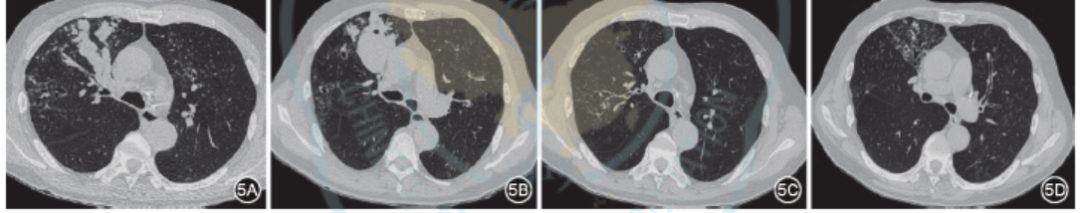

(一)激素治疗

口服激素是ABPA的基础治疗,能有效抑制过度免疫反应,并减轻曲霉引起的炎症损伤。早期应用口服激素治疗,可防止或减轻支气管扩张及肺纤维化。大部分患者对口服激素治疗反应良好,短时间内症状缓解、肺部阴影吸收(图5)。口服激素的剂量及疗程取决于临床分期[2]。有研究提示,中等剂量激素与高剂量激素在治疗效果上相当,同时不良反应更少[48]。对于并发哮喘急性发作期的ABPA患者,推荐中等剂量口服激素,以尽量减少激素带来的不良反应。高剂量激素并不能为患者带来进一步疗效获益,也不会延缓其进展为激素依赖性ABPA的时间[30]。Ⅰ期和Ⅲ期患者使用的泼尼松起始剂量推荐为0.5 mg/kg,1次/d,2周;继以0.25 mg/kg,1次/d,4~6周;然后酌情减量,建议每2周减5~10 mg,可隔日给药[2,30]。治疗时间依据疾病严重程度不同而有所差异,总疗程因人而异。Ⅳ期患者可能需要长期口服小剂量激素维持治疗。合并糖尿病的患者应尽可能减少激素的剂量,并密切监测血糖,及时调整降糖药物[49]。

图5 1例ABPA患者口服激素治疗前后肺部CT影像学变化 5A:治疗前黏液嵌塞征;5B:另一层面显示治疗前黏液嵌塞征;5C:口服泼尼松治疗8周后显示黏液嵌塞征消失,遗留局部支气管扩张;5D:另一层面显示治疗后黏液嵌塞征消失